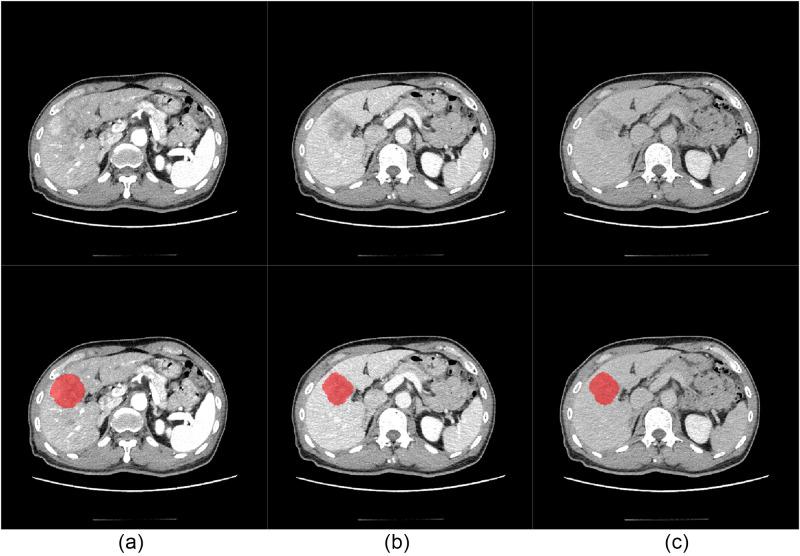

This retrospective study analyzed 174 patients with 187 hepatocellular carcinoma (HCC) lesions. Radiomic features (n = 2264) were extracted from arterial phase (AP), venous phase (VP), and delayed phase (DP) CT images. Key features were selected using minimum redundancy maximum relevance (mRMR), SelectKBest, and least absolute shrinkage and selection operator (LASSO) algorithms. Logistic regression and support vector machine (SVM) classifiers were employed to develop individual phase-specific models and a triphasic fusion model. Model performance was evaluated through the area under the curve (AUC), sensitivity, specificity, decision curve analysis, and other metrics.

The triphasic fusion model demonstrated superior performance. In the testing 1 dataset, the triphasic fusion model achieved AUCs of 0.890 (95% CI: 0.741-1), 0.895 (95% CI: 0.781-1) and 0.829 (95% CI: 0.675-0.984) for Edmondson-Steiner (Ed) grading, Microvascular invasion (MVI) grading, and Satellite nodule (SN) grading, respectively. In the testing 2 (validation) dataset, the triphasic fusion model achieved AUCs of 0.836 (95% CI: 0.739-0.934), 0.871 (95% CI: 0.748-0.993) and 0.810 (95% CI: 0.656-0.963) for Ed, MVI, and SN grading, respectively. The performance of the fusion model was better than that of the single-phase models.